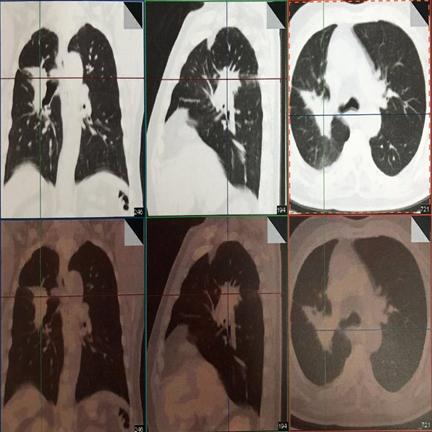

患者刘某某,男,65岁, 13年前因咳嗽、咳痰带血半年就诊,胸部CT示右上肺占位,支气管镜示右上叶前段支气管远端狭窄,活检病理:中低分化鳞癌。诊断:右上肺中低分化鳞癌,T4N1M0,IIIB期。

因二次全麻下气管插管出现哮喘无法手术,于2007年5月30至2007年6月28日进行局部放射治疗,同时给予对症支持治疗。照射剂量PTV(肿瘤外5mm)66GY/22f/30d;GTV(肿瘤边缘)70GY/22f/30d;GTV1(肿瘤内部)77GY/22f/30d;治疗期间,咳嗽缓解、无咯血,血常规 基本正常 范围,按计划完成治疗。

治疗后5年复查,患者偶有咳血,局部病灶纤维化改变

治疗后11年复查,无明显活动后 气喘 。